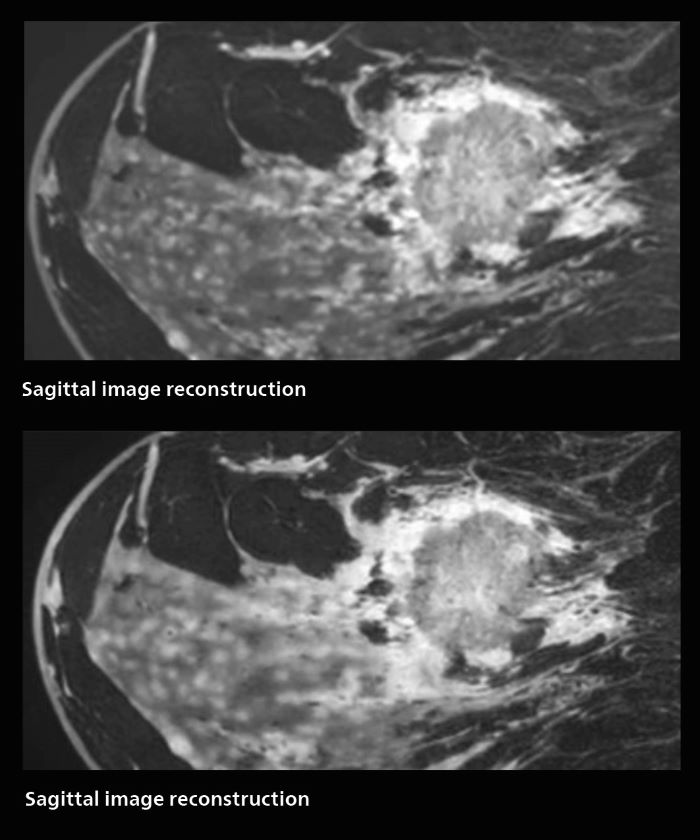

Fast, dynamic breast imaging for diagnostic confidence

Speed and high image quality are also important factors determining the diagnostic value of breast MRI. “When the spatial resolution is not high enough for making the diagnosis of breast cancer, a very difficult decision must be made,” says Dr. Katahira. “Since SmartSpeed now allows us to increase the resolution, we can often easily provide a confident answer. In the past with SENSE we used 1.2 mm isotropic voxels in breast imaging after contrast admission. With Compressed SENSE that is 0.8 mm. Now with SmartSpeed we can acquire 0.6 mm isotropic voxels and the images are so clear that even tiny details are clearly visible.” “For example, we can now scan 20 consecutive, very fast dynamic images of the mammary glands with a single 3-second volume acquisition. This allows us to see how the blood flow is progressing in a very different way.” “The use of SmartSpeed has considerably improved our breast cancer imaging, with higher temporal resolution, higher spatial resolution, and higher SNR compared to the past, when we were using just Compressed SENSE. In addition, the dynamic study is now more useful in diagnosis because the ultrafast dynamic scan can be taken every 3 seconds.”

3D MRI of breast cancer

Scanning was performed with two different voxel sizes. AI enabled volume MRI allows image reconstruction in other directions. Biopsy revealed invasive ductal carcinoma in this patient. Performed on Elition X.

The hospital’s routine ExamCards for breast imaging include: